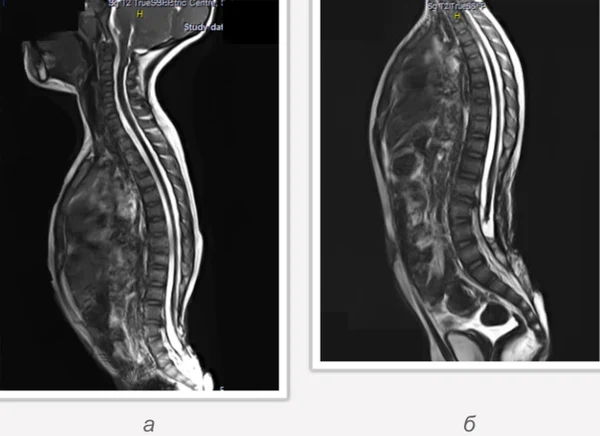

Spina bifida, спинно-мозговые грыжи, диастематомиелия, липоменингомиелолоцеле, фиксированный спинной мозгSpina bifida включают различные типы нарушения закладки и развития нервной трубки на спинальном уровне, что сопровождается незаращением дужек позвоночника и часто сопровождается одновременным пороком развития спинного мозга и его оболочек. Встречаются у 1 на 1000 – 3000 новорожденных. Могут наблюдаться в различных отделах позвоночника, но наиболее часто встречается в пояснично-крестцовом отделе. Незаращение дужек позвонков с наличием грыжевого выпячивания обозначается в литературе по разному: спинно-мозговые грыжи, spina bifida, spina bifida cystica, spina bifida vera, spina bifida typica, spina bifida aperta. Классификация spina bifida aperta: I Рахишизис. II Спинномозговые грыжи. Менингоцеле. Менингорадикулоцеле. Миеломенингоцеле. Миелоцистоцеле. Липоменингомиелоцеле. Основные сопутствующие пороки центральной нервной системы: Гидроцефалия до 65-85%. Аномалия Киари 2. Сирингомиелия.